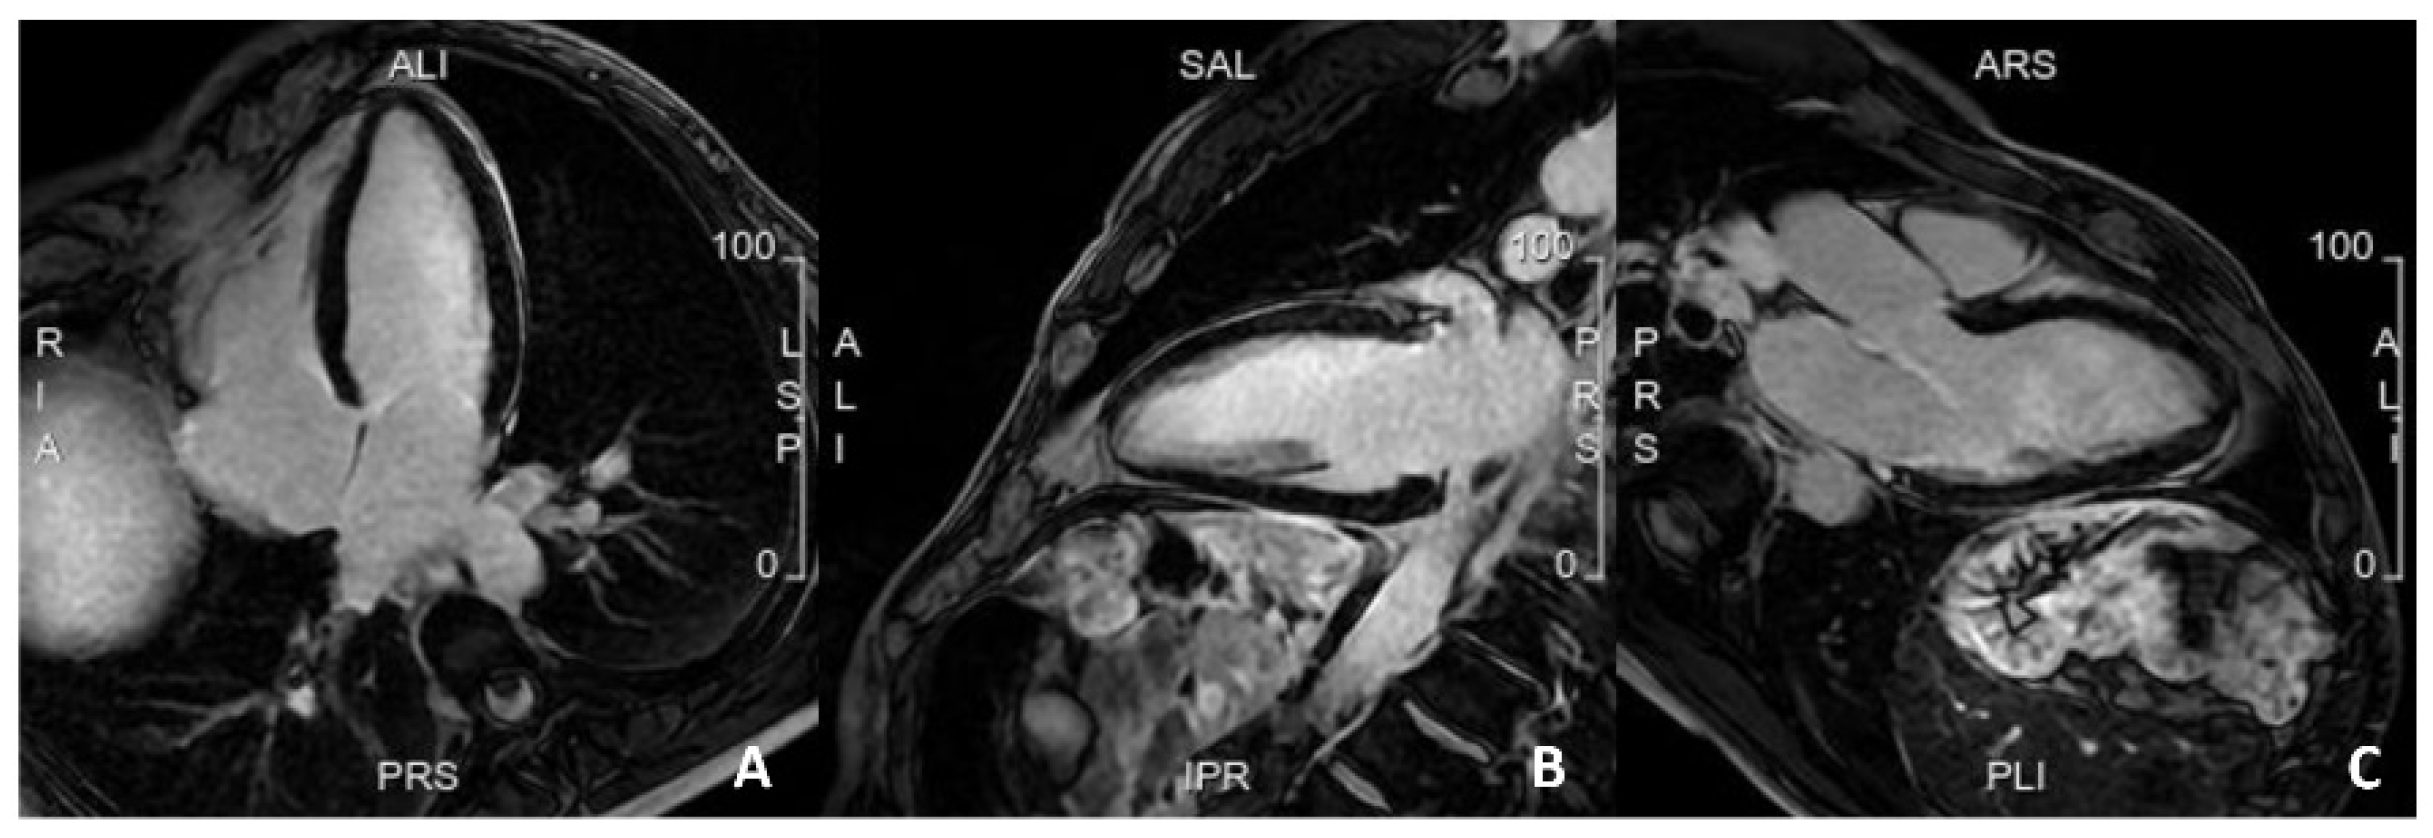

5.3. Advances in MRI for Risk Assessment